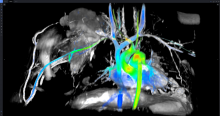

In the conclusion of this 3-part video series on recent advancements in diagnostic radiology, current editorial advisory board member Robert L. Bard, MD, PC, DABR, FASLMS, discusses other advancements in diagnostic radiology and what new technologies are in development that could help in the fight against cancer.

Watch VIDEO PART I: Using 3-D Doppler Imaging and Other Advancements in Diagnostic Radiology

Dr. Bard is internationally known and recognized as a leader in his field. He specializes in advanced 3-D Doppler imaging to detect cancers in numerous organs, including the breast, prostate, and other areas. His images are used to accurately guide biopsies, target therapy and provide focused follow-up after treatment. He is committed to improving non-invasive cancer testing and developing minimally invasive image guided technologies to prevent cancer spread.